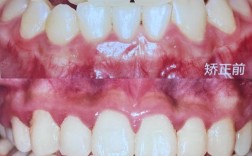

矫正完成的牙齿图片通常涵盖多个维度,全面反映治疗效果,首先是牙齿排列的整齐度,这是最直观的改变:原本拥挤、扭转、错位的牙齿会调整至整齐的弧线,牙列中缝与面部中线对齐,牙间距均匀(如存在牙缝,会通过矫正关闭或保持自然间隙),其次是咬合关系的改善,包括上下牙弓的匹配度(深覆合、深覆盖是否解除)、后牙咬合的稳定性(尖窝交错关系是否正常),以及下颌运动时无早接触或干扰,图片还会捕捉面部软组织的变化,如因牙齿前突改善导致的嘴唇形态更自然、微笑曲线更协调,甚至因咬合功能恢复带来的面部肌肉张力提升。

观察矫正完成的图片时,需从多角度综合判断疗效,正面观重点看牙列中线是否与面部中线(鼻尖、唇珠中点)对齐,牙齿是否呈对称的抛物线排列,牙弓宽度是否协调(如两侧后牙对称,无单侧塌陷),45度侧面观则关注前牙覆盖(上前牙覆盖下前牙的距离,正常为2-4mm)和覆合(上前牙覆盖下前牙的垂直距离,正常为下切牙露出1/3),若深覆盖、深覆合已解除,说明咬合功能得到改善,咬合面观需观察后牙是否有尖窝交错关系,避免“锁合”或“反合”;同时检查牙齿边缘嵴是否连续,确保咀嚼压力均匀分布。